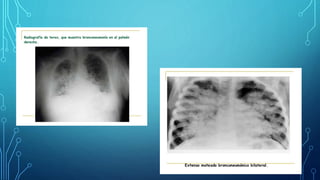

RADIOGRAFÍA

• Condensación lobular o segmentaria única

• Derrame pleural

• Absceso pulmonar

RADIOGRAFÍA • Condensaciónlobular o segmentaria única • Derrame pleural • Absceso pulmonar